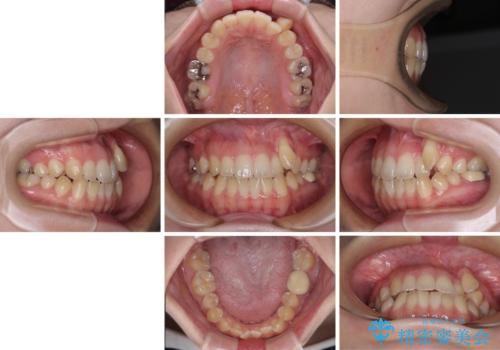

急速拡大装置 狭い上顎骨を拡大してワイヤー装置で八重歯を短期間治療

- 上顎の八重歯やデコボコを気にして来院された患者様です。

上顎歯列が狭窄していたため、急速拡大装置により上顎骨を側方に拡大しながら、ワイヤー装置にて矯正治療を行うこととしました。

上顎骨を拡大することで、八重歯やデコボコを歯列に収めることができ、下顎の歯が外に位置していた奥歯の咬み合わせも改善することができました。

スペースも短期間に獲得できるため、1年程度で治療を終えることができました。